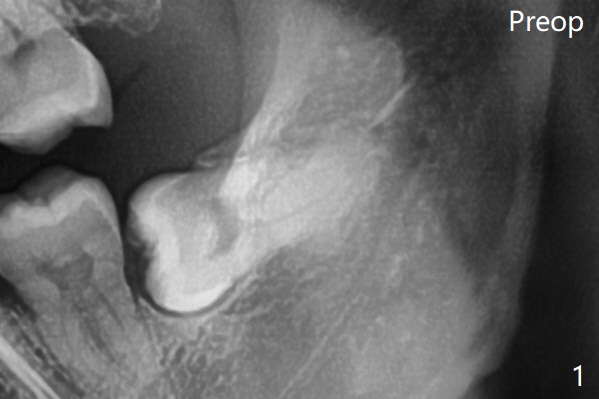

Bone fills the socket 1 year postop (Fig.4). 拔牙顺序: